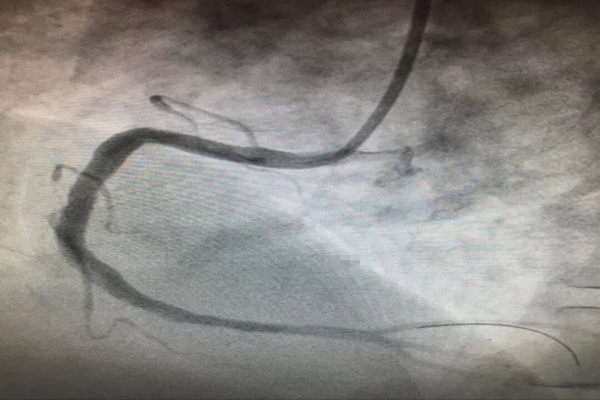

10月16日,入秋的夜晚已是寒冷刺骨,但在介入室內(nèi)我們心內(nèi)科的手術(shù)卻做的是熱火朝天。大家在徐曉輝主任的帶領(lǐng)下連續(xù)奮戰(zhàn)至凌晨2點半,雖然身感疲憊、汗流浹背,但是大家的內(nèi)心卻是無比激動的,因為我們?yōu)獒t(yī)院、為我們心內(nèi)科創(chuàng)造了一個“西北第一”,即“首例Resolute Integrity冠脈支架植入術(shù)”,為西北地區(qū)第一例在術(shù)中應(yīng)用該支架的病例。

運用最新的正弦波技術(shù)制作而成的Resolute Integrity冠脈支架擁有更好的通過性及順應(yīng)性,不僅確保了支架能夠順利通過更加迂曲、成角的病變,而且更加確保了支架植入在大于直徑4.0mm的冠脈內(nèi)能夠貼壁良好,從而保證了在冠脈恢復(fù)TIMI3級血流的基礎(chǔ)上減少術(shù)后急、慢性血栓的發(fā)生。

但是,光有支架還不行,還必須要有能夠駕馭它的人。而此次手術(shù)的患者,不僅僅是病變血管直徑較一般人粗,而且病變部位嚴重成角、迂曲,支架植入手術(shù)是非常困難的。擁有工匠精神的徐曉輝主任不畏困難、勇于挑戰(zhàn),在近20年介入手術(shù)經(jīng)驗的基礎(chǔ)上,運用嫻熟的操作技巧,厚積薄發(fā),成功地完成了我院首例5.0mm直徑冠脈支架植入手術(shù),術(shù)后效果堪稱完美!